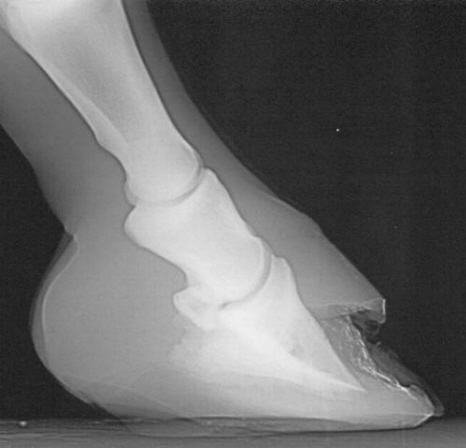

Lose Wand nach Resektion